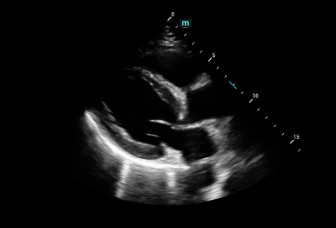

Consona presenta soluzioni nuove e concrete, che aiutano a effettuare diagnosi efficaci con semplicitĂ , rivolgendosi a un'ampia platea di pazienti. La serie mette a disposizione strumenti estremamente avanzati per rimanere all'avanguardia nella diagnosi cardiovascolare.

Galleria di immagini